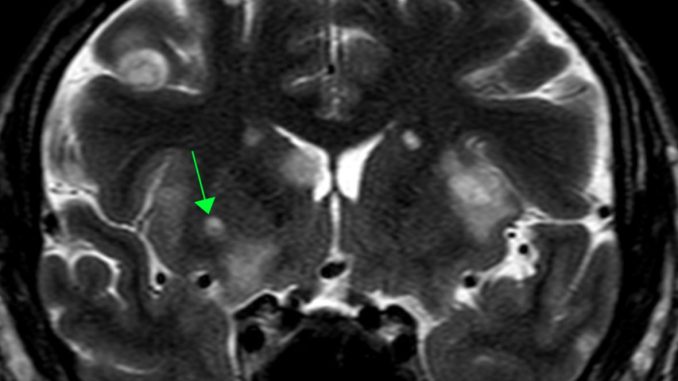

Imagem de ressonância magnética feita no cérebro

“Nosso grupo descobriu e descreveu, pela primeira vez, uma lesão cística com um nódulo periférico dentro dessa lesão acontecendo em pacientes com neurocriptococose. Essa descoberta ajuda a fazer o diagnóstico precocemente e a tratar os pacientes de forma assertiva, evitando a mortalidade, pois é uma doença gravíssima”, explica o professor de Radiologia Marcos Rosa Júnior, do Departamento de Clínica Médica da Ufes.

Destacando a importância do estudo, Rosa Jr. explica que os critérios de diagnóstico de outra doença infecciosa, a neurocisticercose – causada por tênia que se aloja no cérebro –, apontavam que a presença nos exames de imagem de lesão cística com nódulo (comparável a uma pequena bola) confirmava com quase certeza a neurocisticercose. “O que nosso grupo descobriu é que a presença dessa lesão cística com um nódulo dentro não é patognomônico de neurocisticercose, ou seja, não é um sinal tão específico a ponto de diagnosticar essa doença, pois pode acontecer também na neurocriptococose, como descrevemos”, diz o professor.

Imagem: Acervo da pesquisa